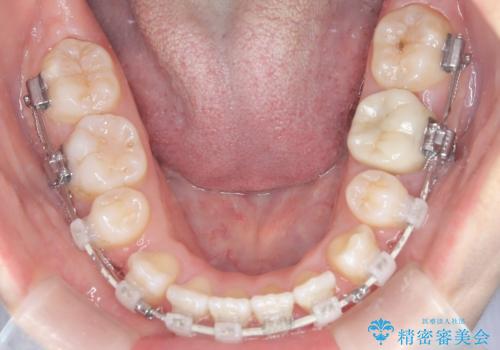

- 前歯のデコボコ(叢生)と、上下の歯が閉じない開口を主訴にご来院されました。精密な検査の結果、歯が並ぶスペースが不足しており、特に奥歯の咬み合わせが安定していないことが開口の原因と判明。患者様と相談し、上下左右の小臼歯を抜歯することでスペースを確保し、審美ワイヤー矯正で全体を整える治療計画を立案しました。これにより、見た目の改善だけでなく、機能的な咬み合わせも獲得することを目指します。

今回の矯正治療では、歯が並ぶスペースを確保するため、上下左右の小臼歯を抜歯しました。装置には目立ちにくい審美ワイヤーを使用し、見た目に配慮しながら治療を進めました。抜歯によってできたスペースを利用して歯を並べ、前歯のデコボコを解消。同時に、歯列全体を動かすことで、上下の歯がきちんと閉じる開口も改善しました。治療期間は約2年間。治療の結果、コンプレックスだった前歯のデコボコと開口が解消され、整った美しい歯並びと、しっかり咬める機能的な咬み合わせを獲得していただけました。